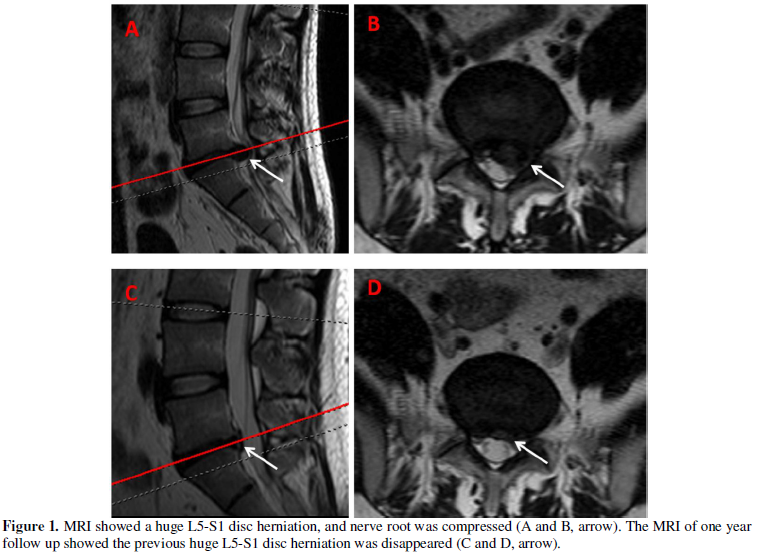

A 26 years old women without medical history presented left leg pain after lifting a heavy object. She can’t stand up because of the sciatic pain, and also complained with numbness of the bottom of left foot. Straight-leg-Raising test showed only 30 degree, and MRI (Magnetic resonance imaging) showed a huge L5-S1 disc herniation, and nerve root was compressed (A and B, arrow). Conservative treatment with rest on bed with lumbar traction, combined with nonsteroidal anti-inflammatory medicine. She had a good compliance at first four weeks. Then, she back to work with mild sciatic pain, and come to outpatient clinic one year after first interview, she said without leg pain now and free to normal work life. The MRI of one year follow up showed the previous huge L5-S1 disc herniation was disappeared (C and D, arrow). Current trials found that surgery may be had an earlier relief of pain, however, few differences were observed in pain and disability between surgical and conservative treatment after one year. Additionally, conservative treatment have advantage of cost saving.